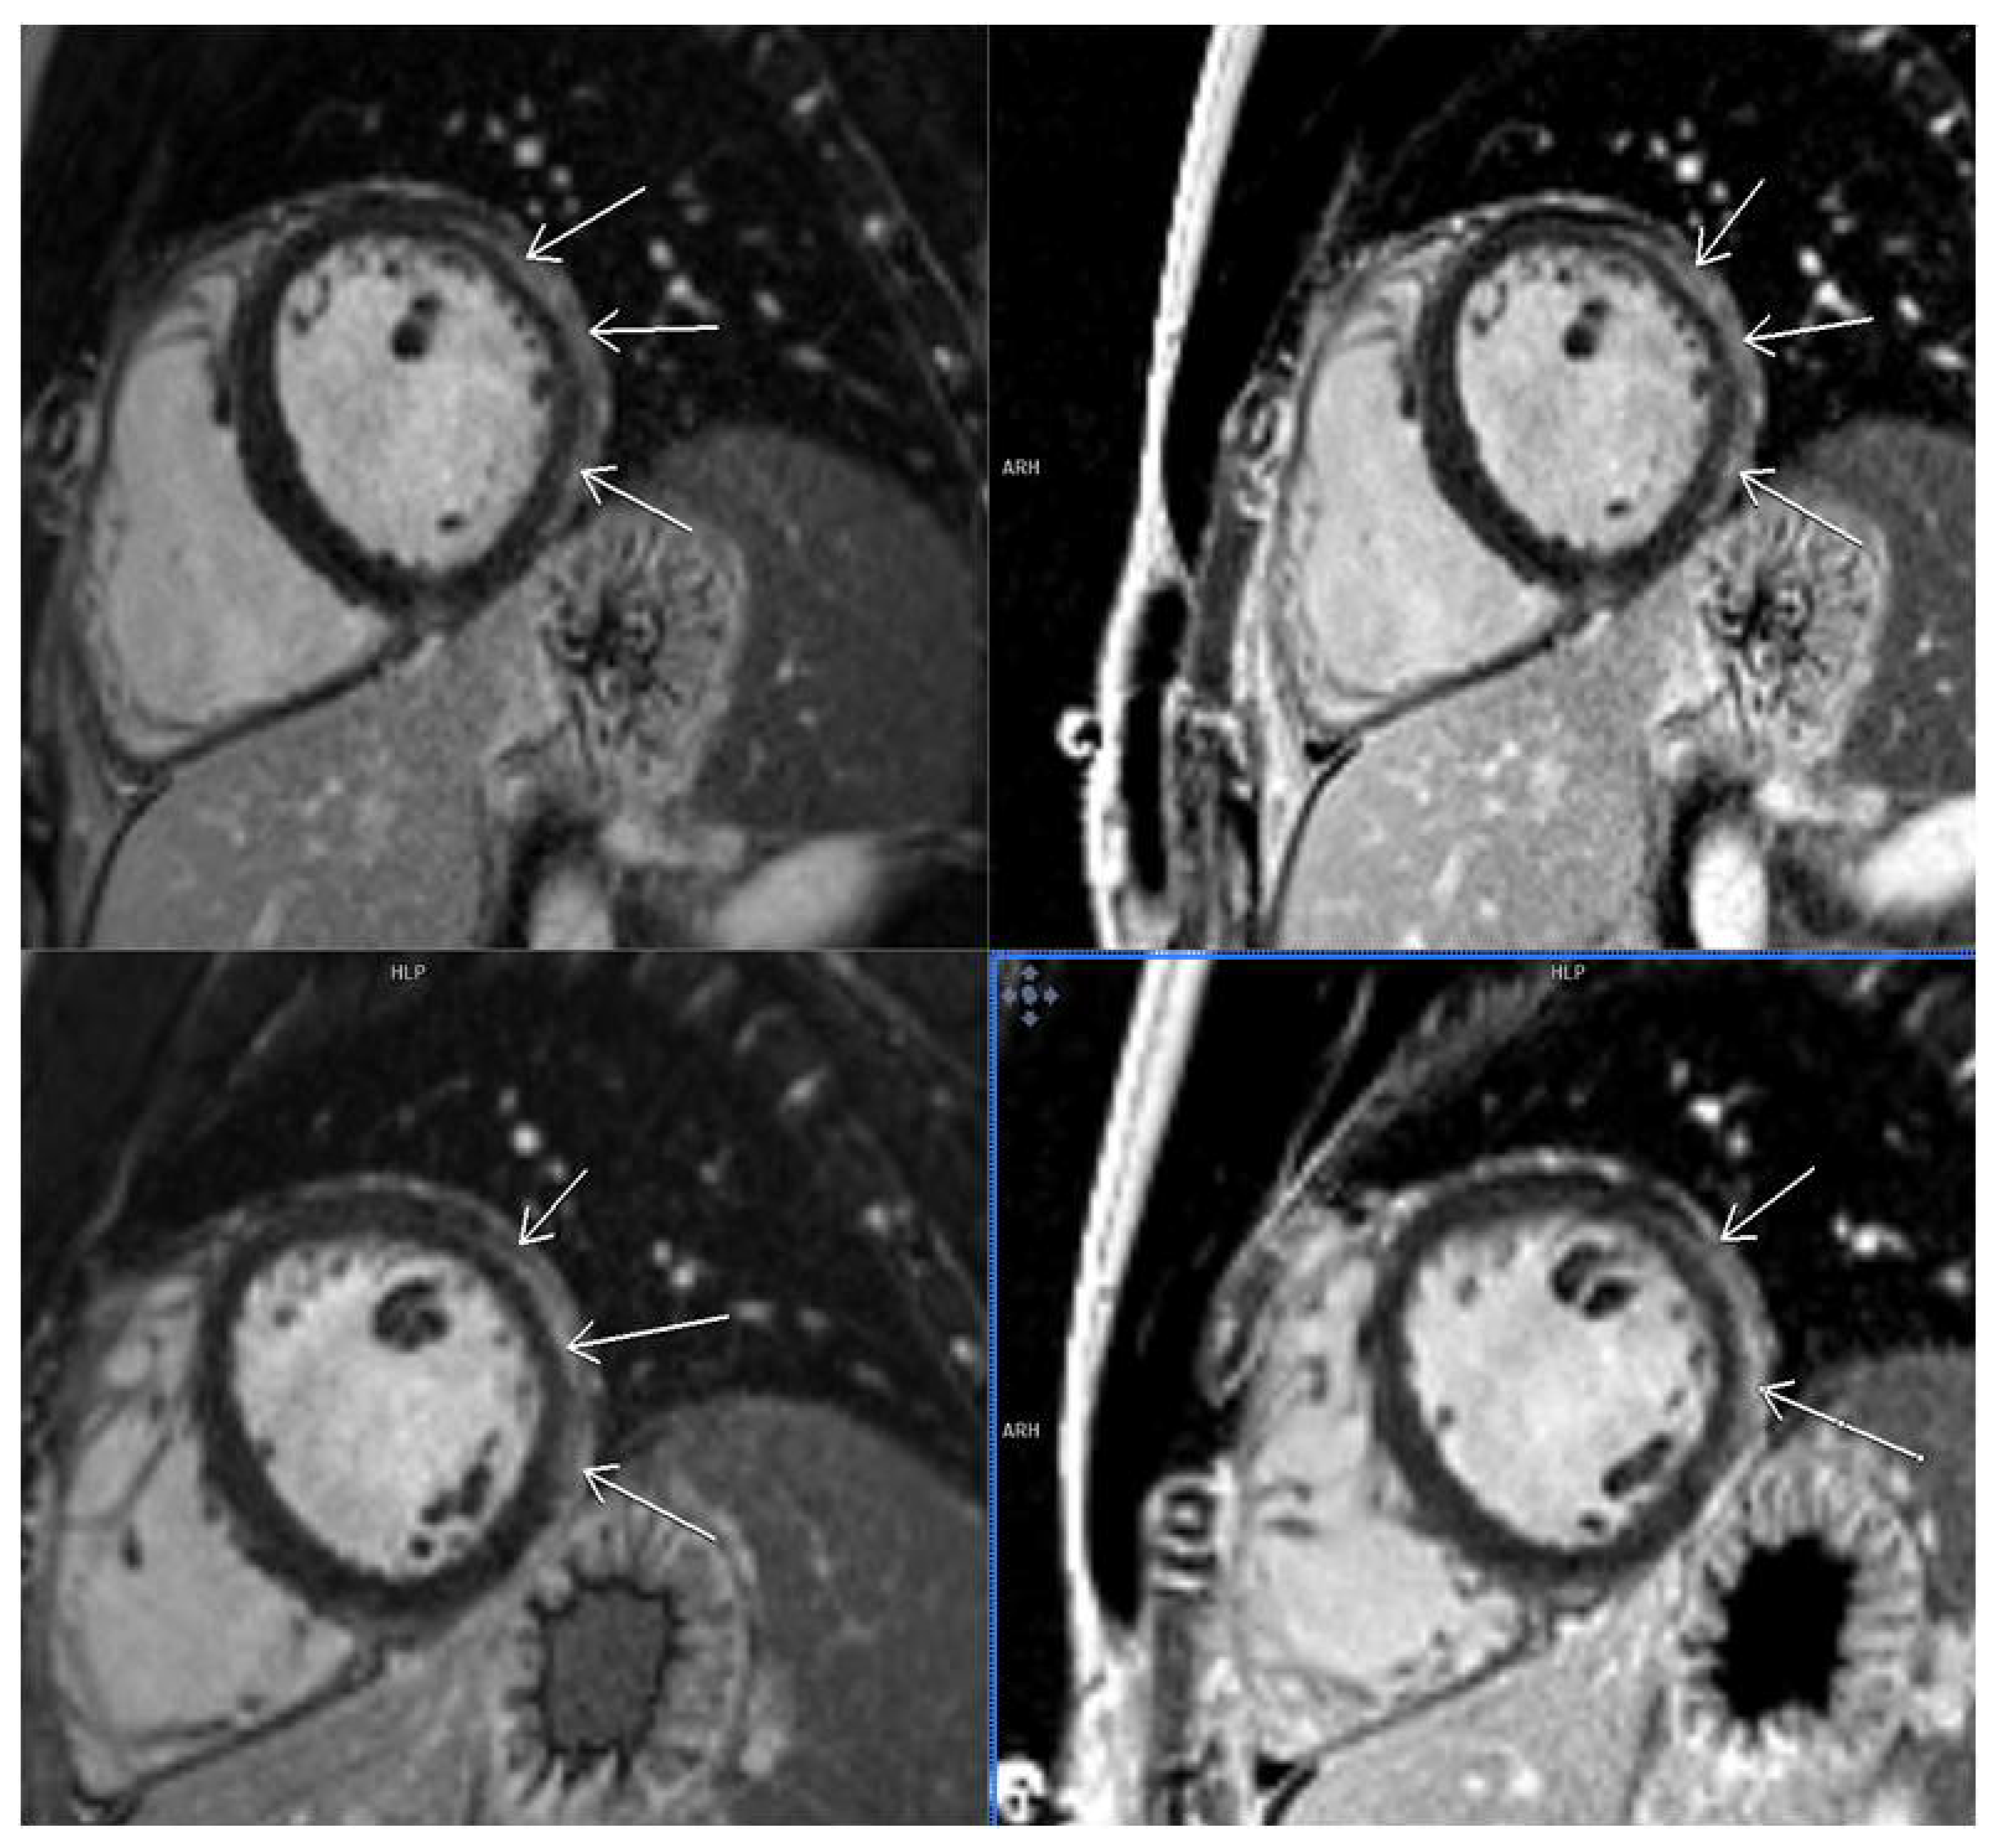

3.2. CMR Findings

3.5. LGE Localization